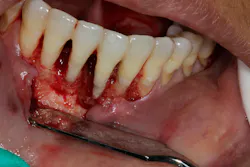

- Proper surgical technique including incision, flap design, and complete detoxification of bony defect and root apices (figures 3 and 3a)